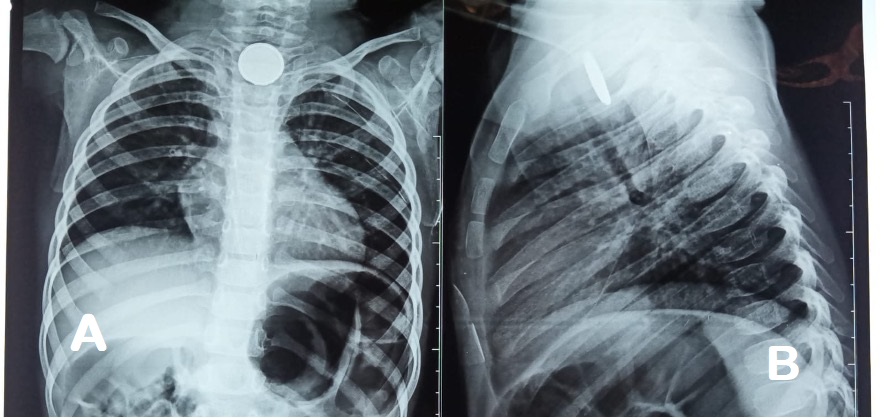

Al octavo día se incrementa la tos y presenta un episodio de hematemesis, por lo cual se solicita radiografía de tórax, que evidencia la presencia de un cuerpo extraño compatible con pila de botón (Ver figura 1A y 1B), por lo que se realiza endoscopía para su extracción (Ver figura 2A), siendo exitosa y evidenciando a su retiro, la presencia de fístula traqueoesofágica de 5 mm en cara anterior de esófago, con tejido necrótico y áreas de fibrina a su alrededor que condicionan una estenosis de tercio superior de esófago en un 20 % aproximadamente (Ver figura 2B), por lo que es referido a hospital de 3er nivel continuar manejo.

Figura 1. A: Presencia de pila de botón en tercio superior de esófago en radiografía anteroposterior de tórax. B: Presencia de pila de botón en tercio superior de esófago en radiografía lateral de tórax.